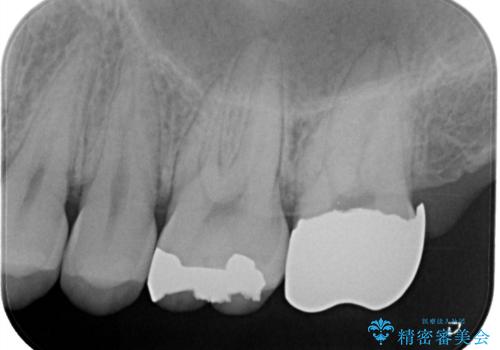

- 歯茎がよく腫れ、痛みが出ることを主訴に来院された患者様です。

レントゲン等から、金属の被せ物が歯にあって作られていないことがわかり、汚れの貯留もみられました。

金属を除去し、虫歯の治療後に型取りを行い、清掃性、審美性に優れたセラミックインレー、セラミッククラウンを装着いたしました。